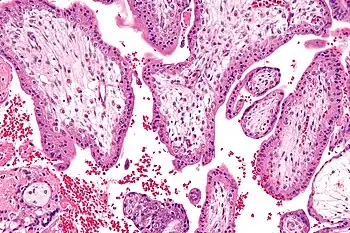

![]() | |

| 7-Dehydrocholesterol is a toxic steroidal metabolite that accumulates in the bodies of those with SLOS | |